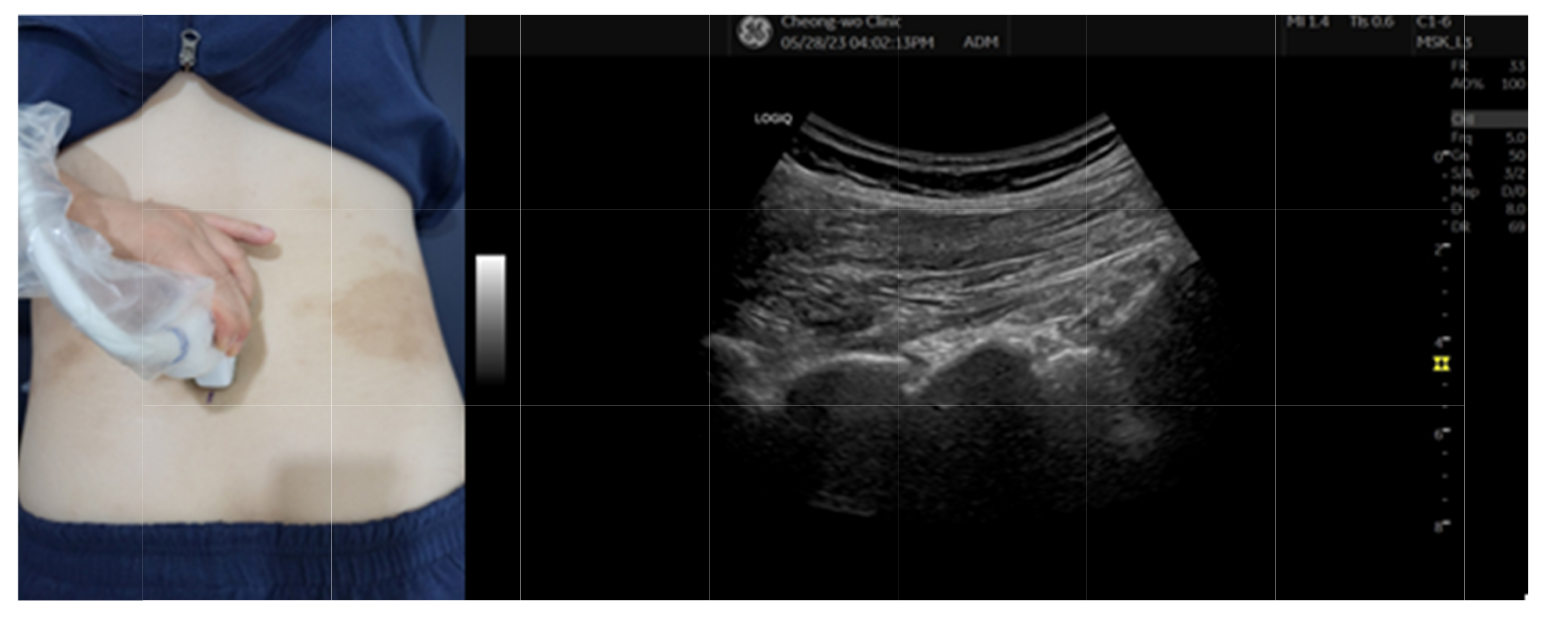

◇ 간접 중재술(초음파 보조 하 내구혈취혈 방법)

① Longitudinal view로 Probe를 환자 허리에 대고, Ner-oaxial view 중 Lamina view에서 시술하려는 레벨을 선정한다.

② 시술하려는 레벨에서 Probe를 안쪽으로 천천히 이동해 Interlaminal space가 보이도록 초음파를 주사한다.

③ 선택한 레벨의 Interlaminal space를 Convex probe의 중심에 두고, 서지컬마커를 Probe 가로와 세로 중심점에 점을 찍는다.

④ 해당 위치에서 영상상 Interlaminal space 위 라미나의 하단과 아래 라미나의 상단을 이은 선까지의 깊이를 확인한다.

⑤ ③의 교점에서 침도를 직자에 가깝게 자입한다. 이때 ④의 자침 심도 전까지만 진침한다.